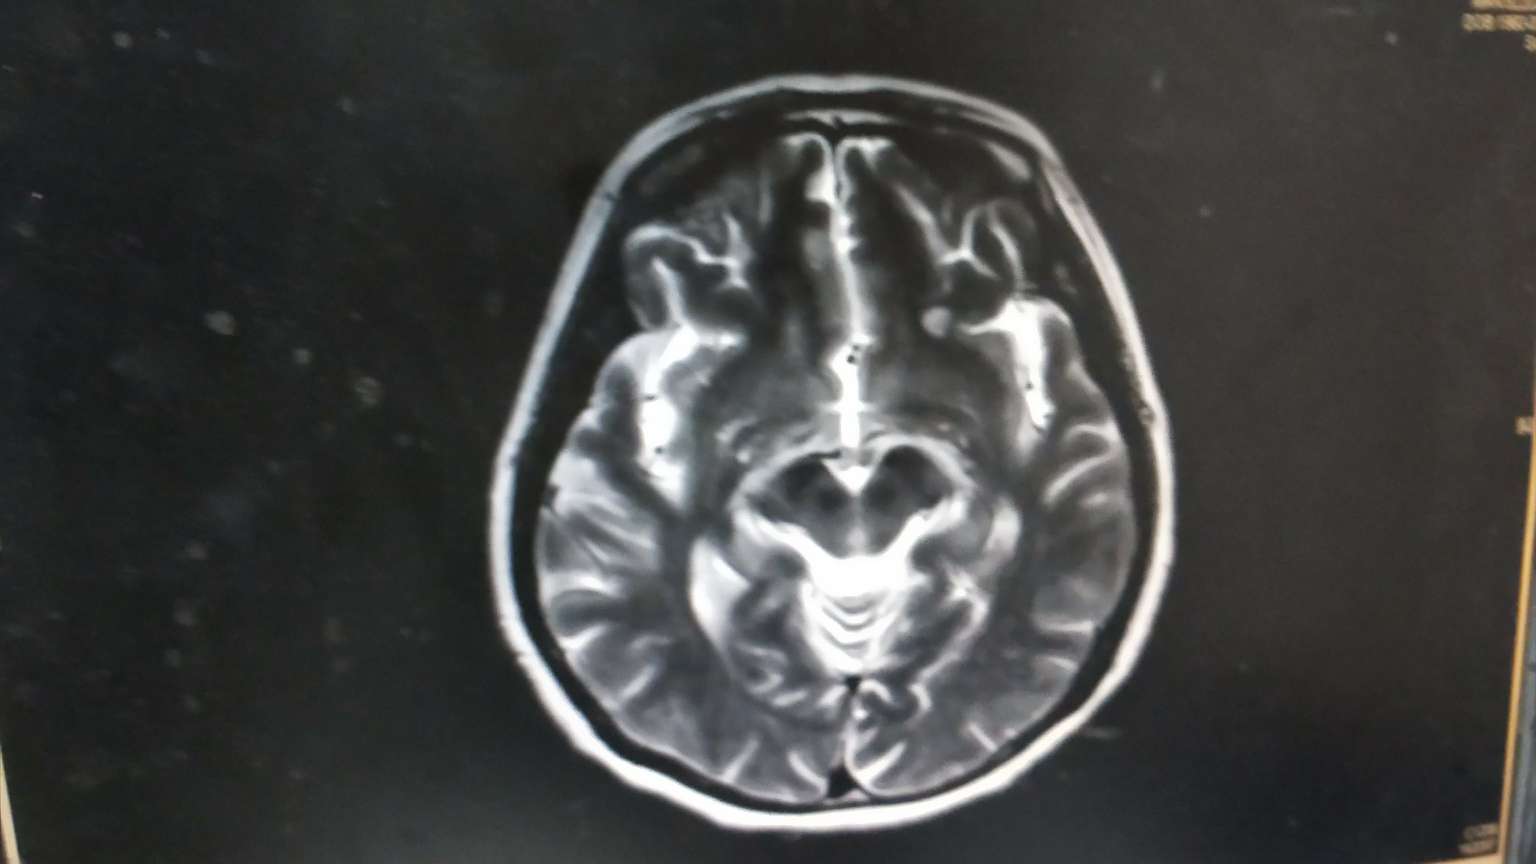

★颅脑左额叶和顶叶结节,双侧基底节区及半卵圆中心多发腔隙灶。